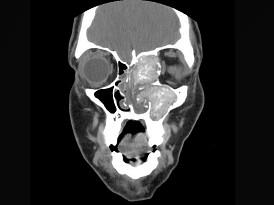

问题 17岁男性,左侧上睑下垂,CT检查如图所示,请选择正确的描述或诊断 ( )

选项 A、考虑为真菌性副鼻窦炎 B、考虑为细菌性副鼻窦炎 C、左侧上颌窦窦口扩大 D、鼻中隔、左侧眶内壁、上颌窦内侧壁骨质破坏 E、左侧上颌窦、筛窦内见软组织块影

答案 ACDE